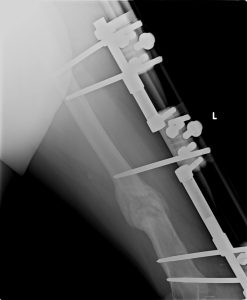

1. Deformite ile birlikte Sert Psödoartroz

Bu tip psödoartrozlar genelikle yetersiz stabilite sonucu oluşmuşlardır. Patolojinin tedavisinde prensip, tedrici olarak deformitenin düzeltilmesi ve bir miktar distraksiyonla (monofokal distraksiyon osteogenezi) kallus oluşumunun stimülasyonudur. Deformite düzeltme prensiplerinden de bilindiği üzere eğer ekstremitede kısalık da mevcut ise menteşeler deformitenin konveks tarafında açı ortay üzerine yerleştirilmelidir. Psödoartroz hattı günde 0.5 mm distraksiyon yapacak şekilde ayarlanmalıdır. Çünkü klinik tecrübemiz sert psödoartrozlarda 1 mm / gün yapılacak bir distraksiyonun ağrıya sebep olacağıdır.